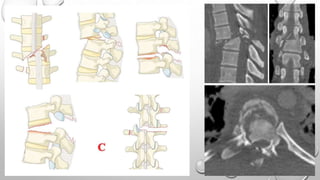

Tipo C

Describe desplazamiento o dislocación.

No hay subtipos.

Como consecuencia de la disociación entre los

segmentos craneal y caudal son posibles varias

configuraciones en diferentes imágenes.

Es combinada con Subtipos A si es necesario.